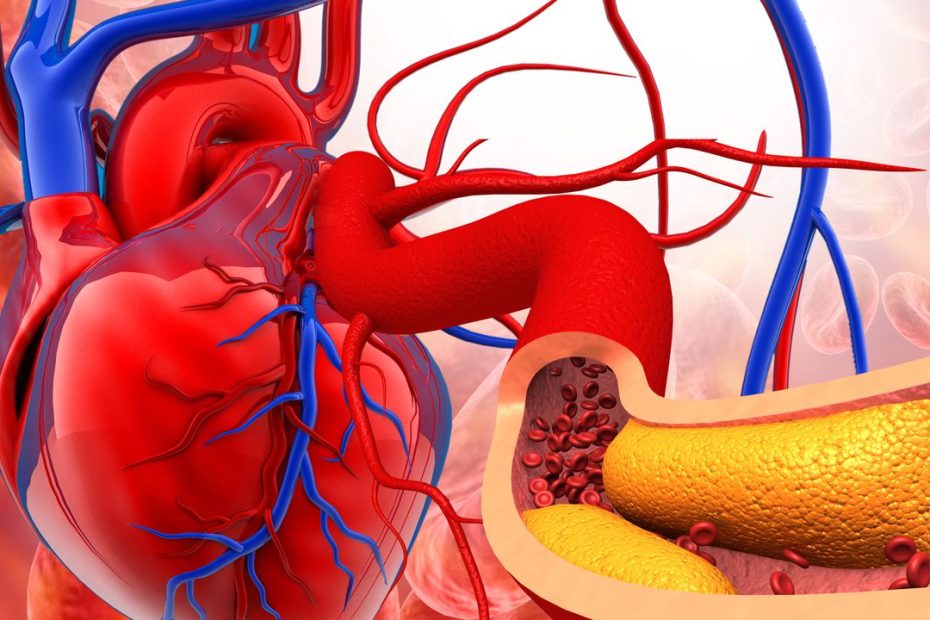

Gaudir d´aquest Cap d’Any mantenint rutines saludables és la millor manera que la teva salut cardiovascular es mantingui en forma. I encara que en aquestes dates solem cometre algun excés, és possible cuidar el teu… Com gaudir d’un Cap d’Any cardiosaludable